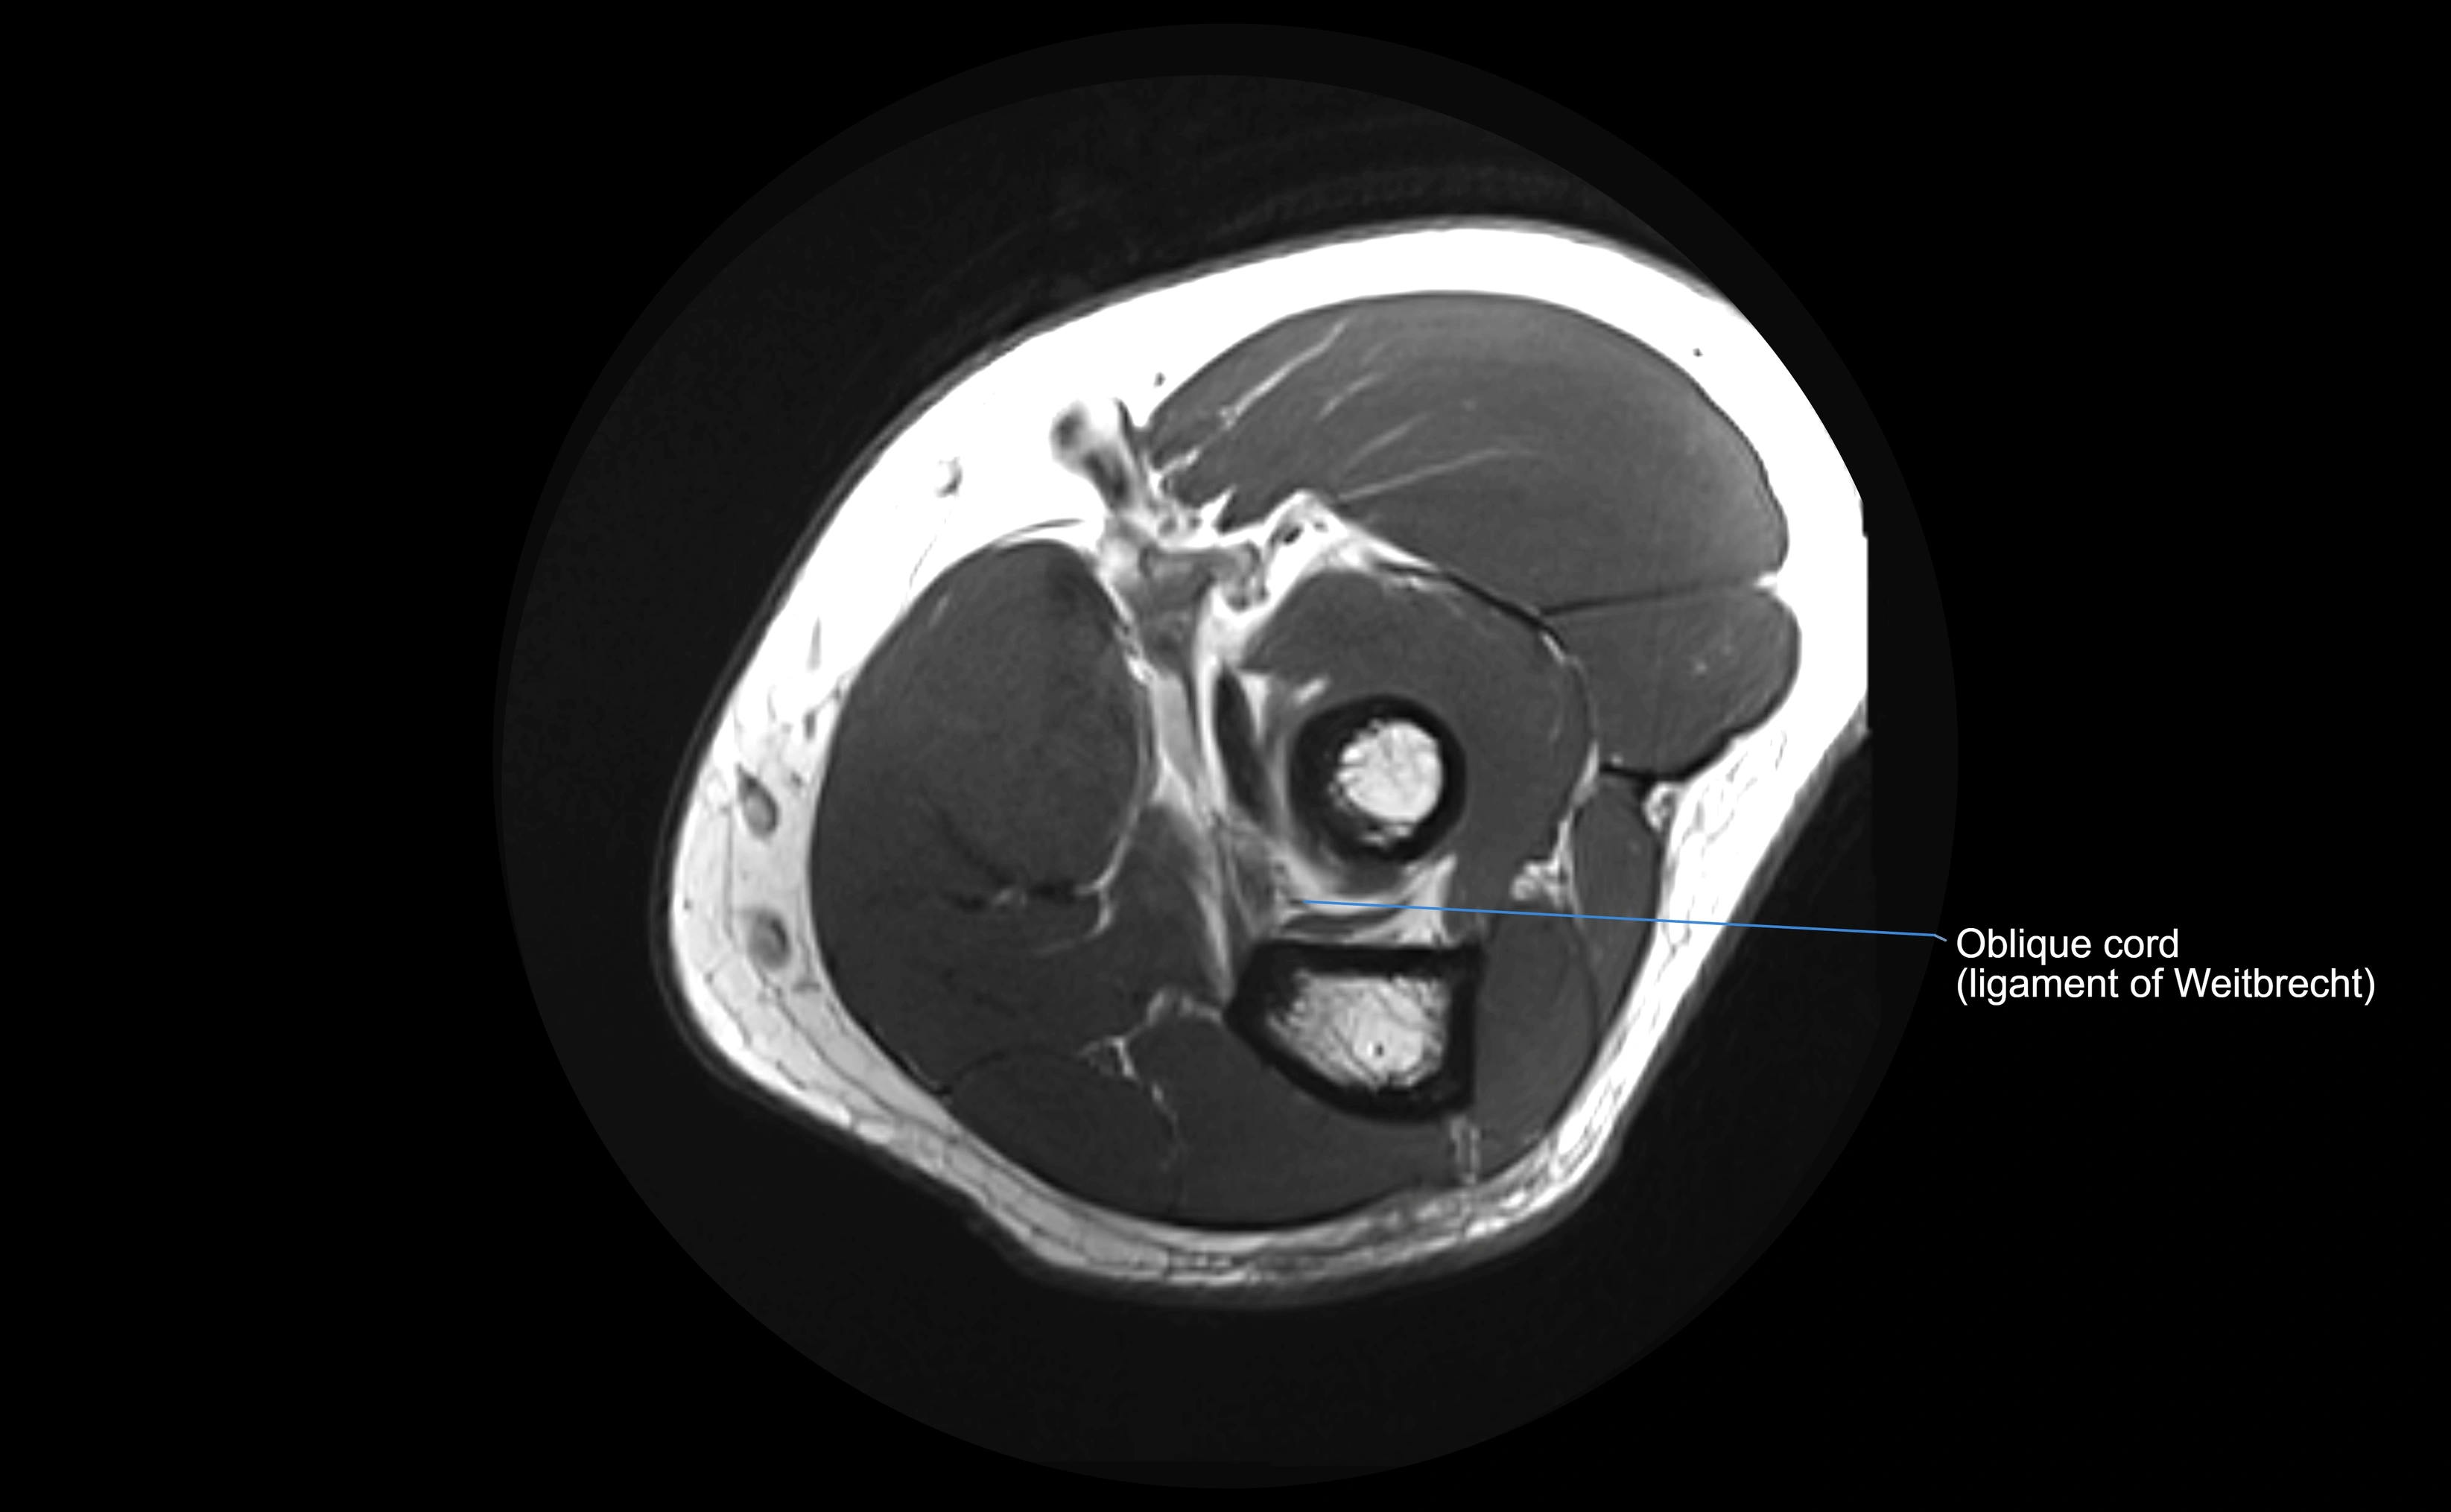

MRI Appearance

T1-weighted images:

• Ligament: low signal intensity (dark), appearing as a continuous band around the radial head.

• Adjacent fat and marrow: bright, creating contrast with the ligament.

• Thickening or disruption indicates injury or fibrosis.

• Joint capsule and synovium seen as thin low-signal lines contiguous with ligament margins.

T2-weighted images:

• Ligament: low signal (dark) with clear delineation from joint fluid.

• Fluid or edema: bright hyperintense, separating or surrounding the ligament in partial tears.

• Complete tear: discontinuity or non-visualization of ligament fibers, often with joint effusion.

STIR:

• Normal ligament: dark band encircling radial head.

• Pathology: bright hyperintense periligamentous signal suggesting edema, sprain, or partial tear.

Proton Density Fat-Saturated (PD FS):

• Normal: dark, well-defined band outlining the radial head.

• Partial tear: irregular or bright hyperintense signal within or adjacent to ligament fibers.

• Joint effusion and reactive synovitis appear bright and are well visualized.

MRI Arthrogram Appearance

• Contrast outlines the proximal radioulnar joint and radial head recess.

• Normal ligament appears as a dark ring surrounding the radial head, containing the injected contrast within the joint cavity.

• Partial tear: contrast extends along the ligament or beneath its fibers.

• Complete tear or subluxation: contrast extravasates around the radial head or ulna, indicating discontinuity.

• Detects capsular defects, instability, or synovial invagination with high sensitivity.